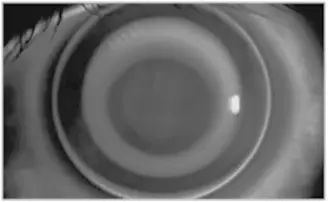

- (A) 螢光圖顯示鏡片中央呈現同心圓狀均勻排列,中央區域略暗、周邊呈規則環形亮帶——接近對齊配戴(alignment fit)的圓形分布,無明顯方向性差異。